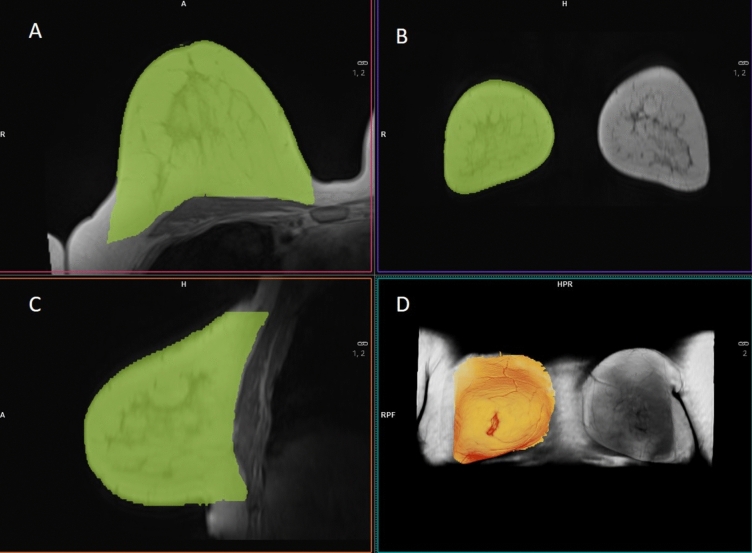

Methods: Breast volume was assessed for 22 women who underwent routine MRI imaging. 3D surface images were acquired using a smartphone's digital texture camera (iPhone 11 Pro Max, Apple, California, USA, 2019). Breast volumes were manually outlined and calculated by two independent investigators using a 3D software tool (Meshmixer 3.5, Autodesk, Inc., 2018). Volume assessments from MRI images were performed by a radiologist using Syngo.via (Siemens Healthcare, Erlangen, Germany, VB50). The agreement between both methods and the inter-observer agreement was calculated with the concordance correlation coefficients and analysed with Bland-Altman plots.

Results: The mean breast volume as determined by MRI volumetry was 771.0 ml on the left side and 763.9 ml on the right side. Utilizing the 3D body surface volume assessment method, the mean breast volume was measured as 660.3 ml (observer A) and 616.8 ml (observer B) on the left side, and 701.9 ml (observer A) and 638.6 ml (observer B) on the right side. Although a high correlation was observed, differences in volume measurements appeared more pronounced in cases of larger breast volume.